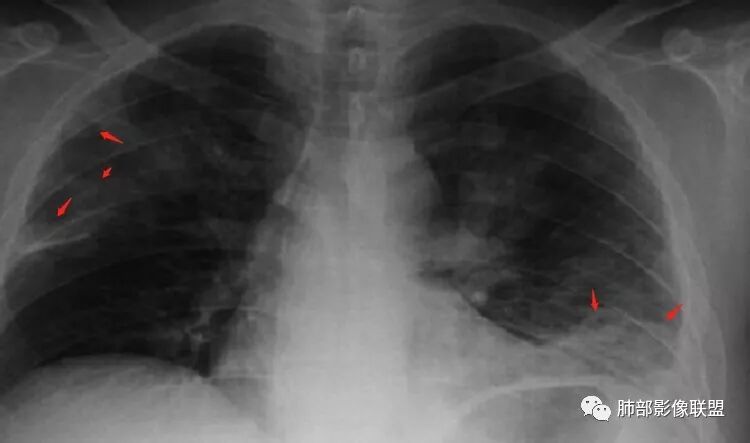

南边:患者男,44岁,以“发热1周伴咳嗽、咳痰3天” 入院。现 病 史:患者入院前1周无诱因出现寒战、发热,体温最高410C,伴肌肉酸痛、恶心、呕吐,就诊于我院, 血常规示白细胞及中性分类增高,予头孢呋辛静点1天,并口服抗生素等药物治疗。患者仍有发热,入院前3天出现咳嗽、咳暗红色血痰,伴左侧胸痛,咳嗽时加重,查胸片后收入我科。初学者:就是脓肿的话,也是坏死。然后肉芽肿边缘的壁;早期的话,它不会形成那种中央坏死壁强化的这种典型表现,但是它的特点是它很快会变化,所以有的时候不是很确定的时候,可以看那个随访。有没有高热,一般会这样判断是不是囊肿。但这个人因为肺部本身有病变,所以说,肝内的这个病变就没有办法鉴别了,那可以看一下他随访有没有变化,这个可以判断囊肿,就是从CT上它的这个壁,有的时候不是很好看,尤其是他脓肿,它形成的话,它有几个期。期不一样,它的壁的厚度、中间的坏死都不一样,所以有的时候它并不是特别的均匀,一般囊肿的话呢,我们会觉得它的分界跟周围的分解和非常的清楚,因为囊肿它是真壁。

南边:胸膜下,类圆形,边界清,内有坏死,典型的反晕征,支气管壁增厚不明显,支持血道来源脓毒栓子所致梗死、感染

血道来源没问题

左下叶大片类似病灶

肺克雷白杆菌——砖红色痰